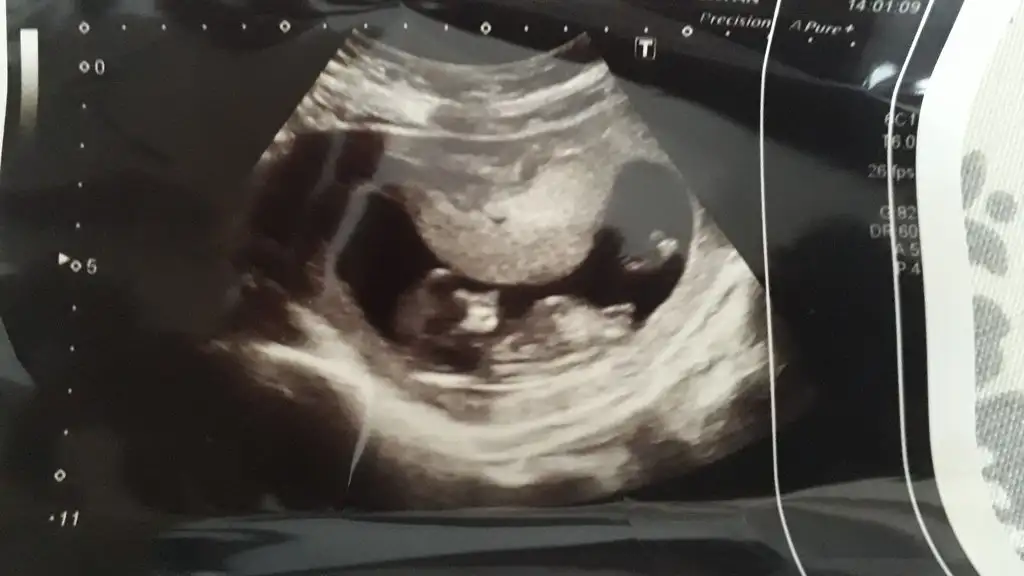

Slm banada yardımcı olurmusunuz dr net bişey demedi daha çok kafam karıstı... Ikra meyra Ikra meyra

Doktorumuz soylemiyor kimseye 16 dan once. Hayirlisi bakalim. Bir kizim var zaten ilk once saglikli olmasini diliyorum Rabbimden

Gönlünüzdeki saglıkla olur inşallah benimki tahmin canım başka arkadaşlarda yorumlar 😊😊